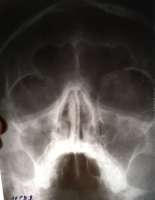

Друзья, поясните пожалуйста за рентген? Лор сказал, что это ринит, но не может же ринит уже 9 ЛЕТ! мучать мой носик?

>>799841

Что-то обе верхнечелюстные и левая лобная пазуха выглядят хреновато. И перегородка чуть кривая

Аноним 09/11/18 Птн 08:03:15 799867180

>>799866

Либо лобной вообще нет, непонятно

Аноним 09/11/18 Птн 08:08:23 799870181

>не может же ринит уже 9 ЛЕТ! мучать мой носик?

что же ему помешает?

Аноним 09/11/18 Птн 09:10:38 799880182